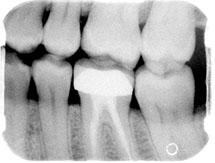

Before/After Photos